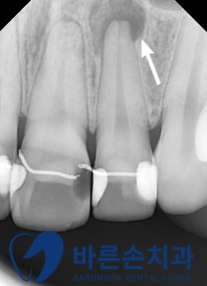

좀 더 정확한 확인을 위해 특정 부위에 치근단 촬영을 추가로 진행하였습니다

치근단 촬영을 통해 통증의 원인이 치근단 염증이라는 것을 확인하였고

근관치료(신경치료)를 시행하기러 하였습니다.